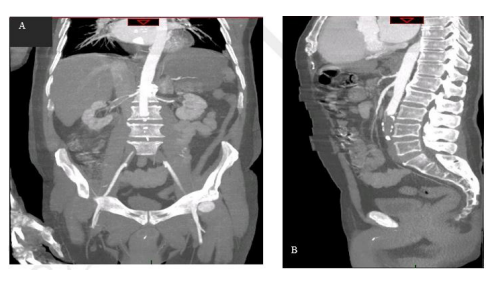

Después de su descompensación, le fue realizada una angiotomografía de abdomen que evidenció oclusión aórtica por gran trombo a nivel infra-renal, con interrupción del flujo hacia las arterias ilíacas y sus ramificaciones, además de escaso medio de contraste endoluminal en arterias femorales por llenado mediante circulación colateral (imágenes 2 y 3).

Imagen 3 Angiotomografía de abdomen. A: corte coronal, evidencia interrupción del flujo de la aorta abdominal por debajo de las arterias renales. B: corte sagital, interrupción del flujo de la aorta abdominal a nivel de L3 aproximadamente.